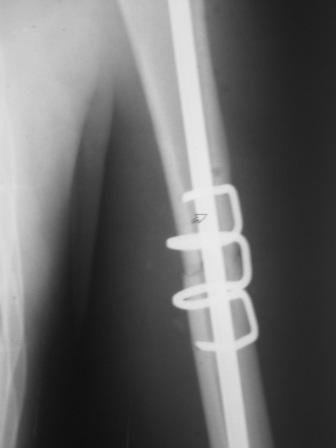

Перелом нестабильный, тактика - если позволяет сосояние больной, оперативное лечение. Как пример см. ниже, можно без скобы - стяжки с ЭПФ.

Представленный способ, функциональный, данная больная в качестве внешней иммобиллизации в течение 3-х недель полльзовалась косыночной повязкой, востановление функции плеча полное. Правда травма изолированная, но операция выполнялась через три недели после травмы, тот час после обращения ко мне - иногородняя.

Да, как раз блокированная пластина и стоит, не синтезовская метадиафизарная, Рыбинская, но на порядок дешевле, а профилактика всех осложнений - в данном конкретном случае, начало ранней на вторые сутки - после удаления дренажа разработки движений в смежных суставах. Если же идти с ревизией т.е. всё равно, открыто как вариант небольших разрезов при поперечном переломе можно и комбинированный мос (см.на вкладыше), хотя думаю для такого способа перелом всётаки низковат.

Всё правильно, просто я несколько разрозненно пытался сказать на частных примерах, то , что Вы систематизировали. Совершенно верно данный перелом можно и так и эдак, наиболее оптимально антеградное штифтование, хотя я бы предпочёл пластину LCP(просто - ну лучше у меня это получается и всё, а больному не вредит тот же функциональный способ). А низковато для неблокированного штифтования с конструкциями с термомеханической памятью, то, что представленно на втором снимке.